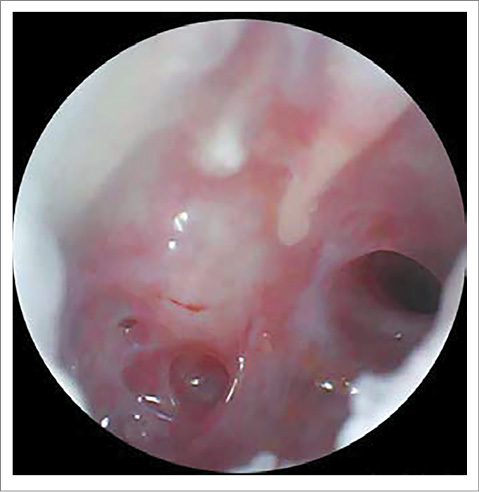

AD – послеоперационный рубец в заушной области без признаков воспаления. При отоскопии: наружный слуховой проход широкий, свободный. Визуализируется тотальная перфорация БП, определяется рукоятка и короткий отросток молоточка. Отмечается васкуляризация слизистой оболочки медиальной стенки барабанной полости, уменьшение зоны некротических изменений (рис. 8).

Рис. 8. Отоскопическая картина справа перед выпиской: васкуляризация слизистой оболочки медиальной стенки барабанной полости, уменьшение зоны некротических изменений.